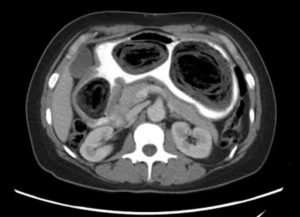

Computed tomography (CT) of the abdomen and pelvis with oral and intravenous contrast was ordered to evaluate her symptoms. The CT showed three large collections of ingested material seen as hypodense material with circular rings surrounded by the hyperdense oral contrast (see red outlines). These findings are consistent with bezoars, the largest of which measured 11.5 x 7.8 cm. There was also thickening of the gastric wall (see blue outline), most notably at the pylorus, consistent with partial obstruction.